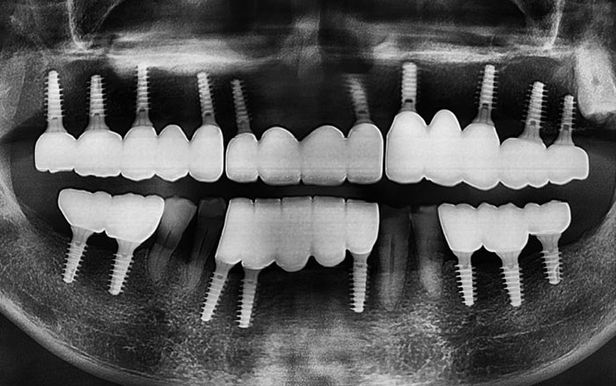

위아래 틀니를 사용하다 무절개 임플란트로 새로운 치아를 갖게 된 엑스레이 전과 후 모습.

틀니를 사용하다 무절개 임플란트 수술 당일에 즉시 최종 보철물을 장착하게 된 모습.